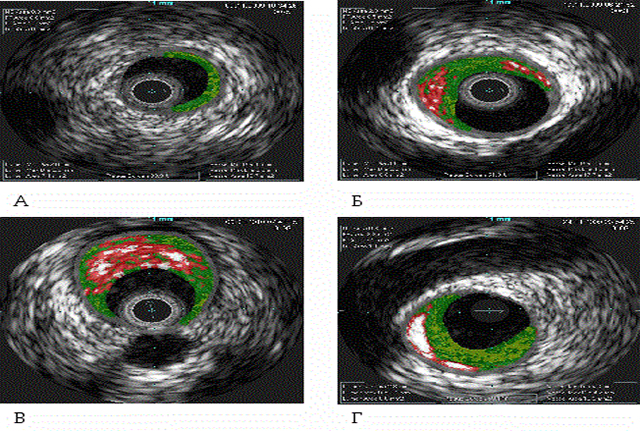

Подавляющее большинство приходит за помощью уже тогда, когда предстоит процесс серьезного лечения, и осложнения атеросклероза не только мешают нормальной трудоспособности, но и приводят к нарушению двигательной активности, или полной инвалидизации. Примерные отличия состояния сосудов на разных стадиях можно увидеть на фото.